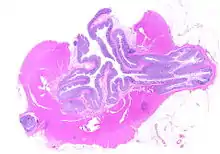

The precise mechanisms by which diverticula are formed are unknown.[1] Multiple theories have been proposed including genetic susceptibility, diet, intestinal motility, changes in the microbiome, and inflammation. One leading theory suggests that diverticula form in weakened areas of the colon wall that are subjected to increased pressure.[1] The strength of the colon wall is known to decrease with age.[1] Previous theories proposed that impacted fecal matter and certain foods would get stuck in diverticula (thereby causing trauma), which caused poor blood flow, death of the affected intestinal wall cells, and intestinal perforation.[1] Newer theories have called this paradigm into question.[1]